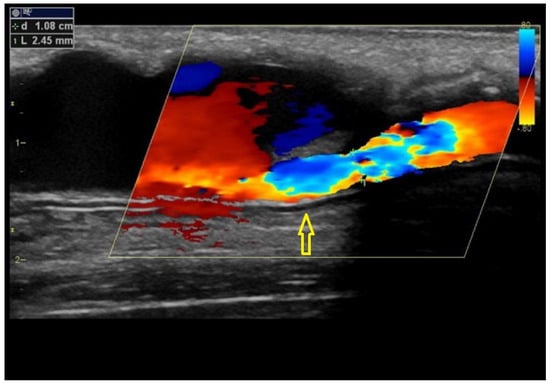

5. Significant Stenosis Definition by Ultrasonography